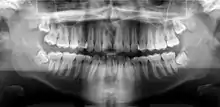

A panoramic radiograph of a 9 year old in mixed dentition

A panoramic radiograph is a panoramic scanning dental X-ray of the upper and lower jaw. It shows a two-dimensional view of a half-circle from ear to ear. Panoramic radiography is a form of focal plane tomography; thus, images of multiple planes are taken to make up the composite panoramic image, where the maxilla and mandible are in the focal trough and the structures that are superficial and deep to the trough are blurred.